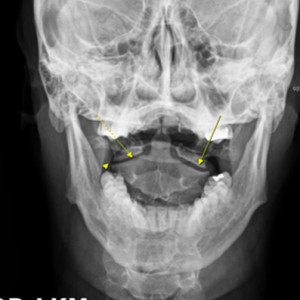

안면 두개골 엑스레이 검사

Submento Vertex View 포함

안면 두개골 CT

경추 1,2번의 변위 파악

부정교합검사

1,2,3단계 부정교합 유무 파악